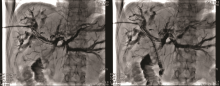

李勇:最终我们选择的治疗方案是胆道支架置入术联合碘125放射性粒子条治疗。如图3所示, 通过前期手术留置的PTCD引流管引入粒子条, 粒子条远端进入左肝管的一个主要分支、近端位于右肝管内; 从留置血管鞘应用双导丝引入一根超滑硬导丝, 沿硬导丝在左右肝管送入80 mm× 8 mm胆道支架一枚。利用支架膨胀张力使留置粒子条固定在胆道内, 然后引入导丝经已放置金属支架网眼进入胆总管、十二指肠, 建立轨道; 使用80 mm× 6 mm球囊扩张支架网眼后引入6F-Guide导管至胆总管中段, 沿导管送入一内装碘125的粒子条; 沿硬导丝在右肝管-胆总管送入80 mm× 8 mm胆道支架一枚。术后造影如图4所示。术前术后对比可以看到术后胆道情况明显好转。术后1个月复查CT(图5)示:与术前比, 肝内部分胆管轻度扩张, 以右叶为著, 左右肝管至胆总管下段内见支架植入, 支架内未见明显软组织影充填。